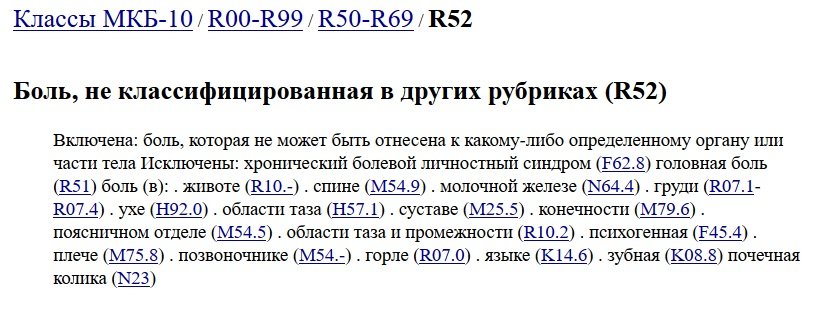

Код мкб 10 атерома головы

Код мкб 10 атерома головы 109 фото